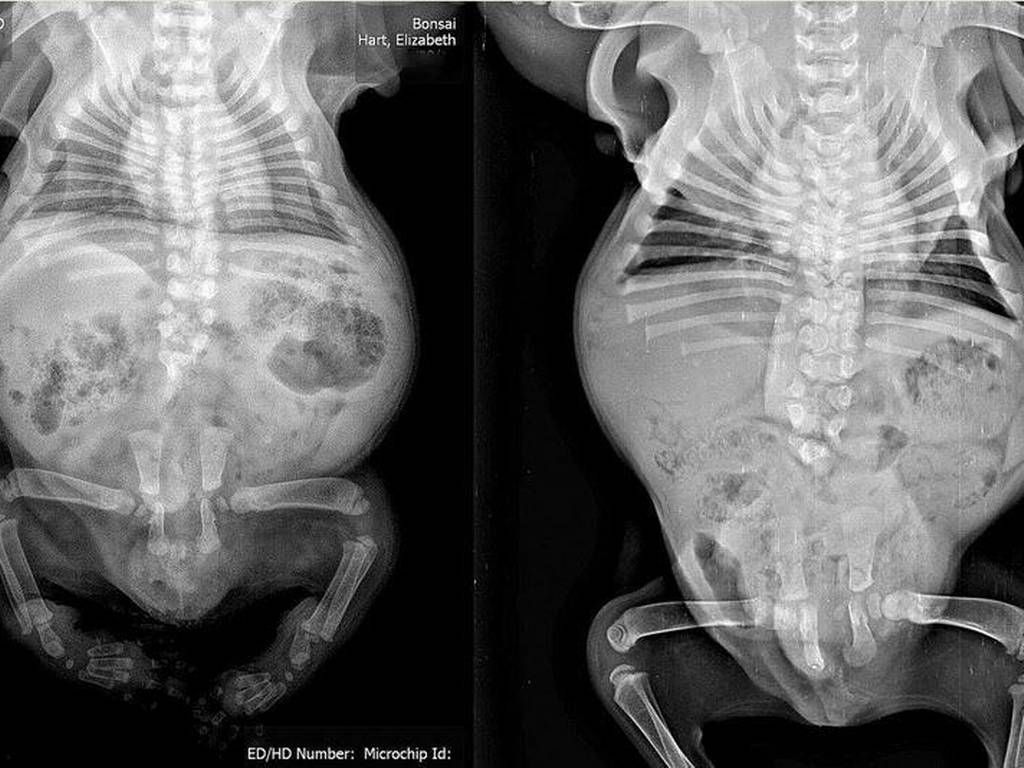

"Bonsai" es un perro bulldog de tres meses de vida que nació con una enfermedad en sus extremidades por la que debieron amputarle casi la mitad de su cuerpo.

El perrito tuvo "síndrome de regresión caudal", y luego de una exitosa operación le han enseñado a moverse con su nuevo cuerpo, pero aún hacen falta fondos para pagar su rehabilitación.

La radiografía de Bonsai